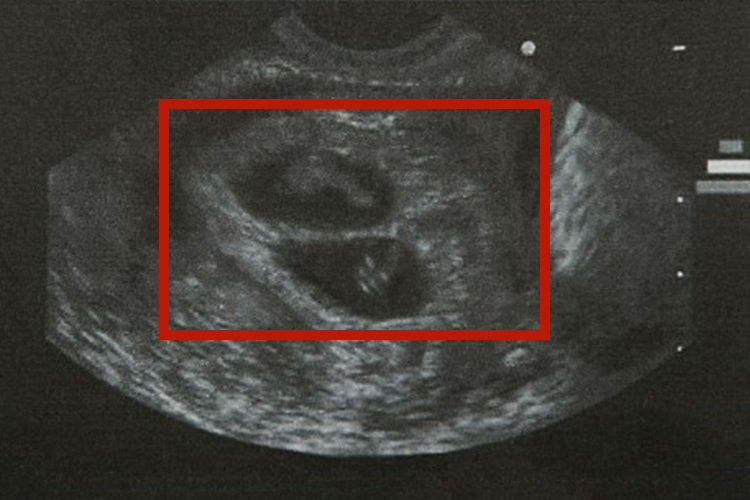

同卵和异卵B超的影像表现存在区别,具体如下:

异卵:异卵B超可见两个受精卵形成各自独立的胎盘、胎囊,它们的发育可以紧靠与融合在一起,但两者间的血液循环并不相通,胎囊之间的中隔由两层羊膜及两层绒毛膜组成,有时两层绒毛膜可融合成一层。